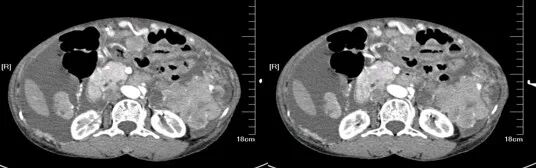

大肠癌

大肠癌是常见的恶性肿瘤,包括结肠癌和直肠癌。大肠癌的发病率从高到低依次为直肠、乙状结肠、盲肠、升结肠、降结肠及横结肠,近年有向近端(右半结肠)发展的趋势。其发病与生活方式、遗传、大肠腺瘤等关系密切。发病年龄趋老年化,男女之比为1.65:1。

升结肠癌并广泛转移